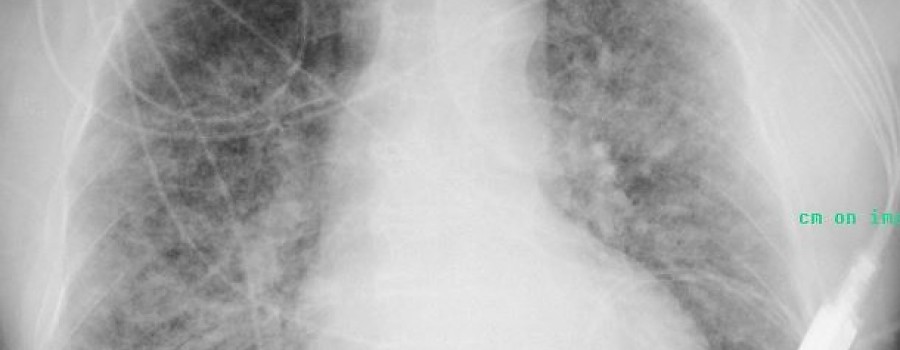

Lungenödem nach Inhalation von Salpetersäure

Respiratorisches Versagen bei Inhalationstrauma mit Salpetersäure